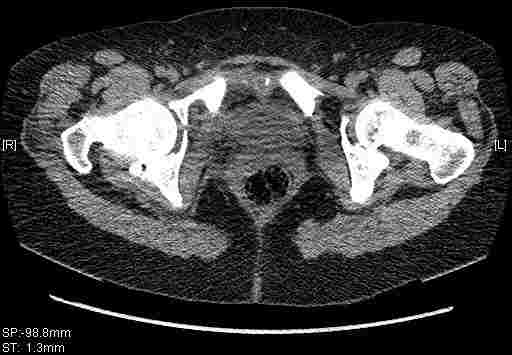

Re: Т-образный перелом вертлужной впадины

Удалось сегодня вывести пациентку в соседнюю больницу, где есть кт. Срезы сделаны только горизонтальные.